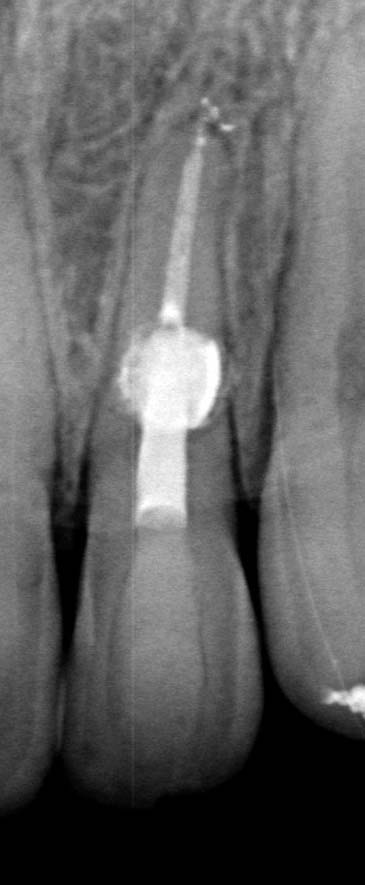

The X-ray snapshots showed signs of internal resorption in tooth 2.2.

The CBCT revealed intraroot perforating resorption on the vestibular root surface. In addition, a possible cause of resorption was identified as Oehlers' Type I invagination (1957), which was based on the radiological findings. According to the classification, Type I invagination is covered with enamel and is located within the coronal part, extending no further than the enamel-dentin junction. The authors believe that the infected invagination zone with subsequent creeping infection of the root pulp brought about the resorption. The response to the cold stimulus was very insignificant, especially in comparison with tooth 12. This made it clear that an irreversible destructive process is going on in the damaged tooth. Since the patient was planning orthodontic treatment and the resorption process could grow worse, it was decided to conduct endodontic treatment.

The diagnosis presented some difficulties and it was necessary to discriminate between internal and external resorption, as they require dififerent treatment tactics. While external resorption provides for either observation or surgery, depending on the extent of the defect and location, internal resorption often implies endodontic treatment.

In favor of external resorption was the shape of the defect, with the wider defect facing the bone, the shape of the defect was not rounded, which would be characteristic of internal resorption.

Also, there were signs in favor of internal resorption. The defect was below the cervical part, which is not typical of external cervical resorption. The response to cold stimuli reduced, which is not characteristic of external resorption, as it affects the pulp only in the last stages of tooth structures decay. Furthermore, the X-ray obliteration of the root canal beyond the resorption area is not characteristic of external resorption. Visit 1: Pre-op X-ray plus anesthesia with sol. Ubisthesini 4% -1 ml, isolation with rubberdam. The access was made as close as possible to the incisal edge. When opened, at first glance the pulp chamber looked quite II.